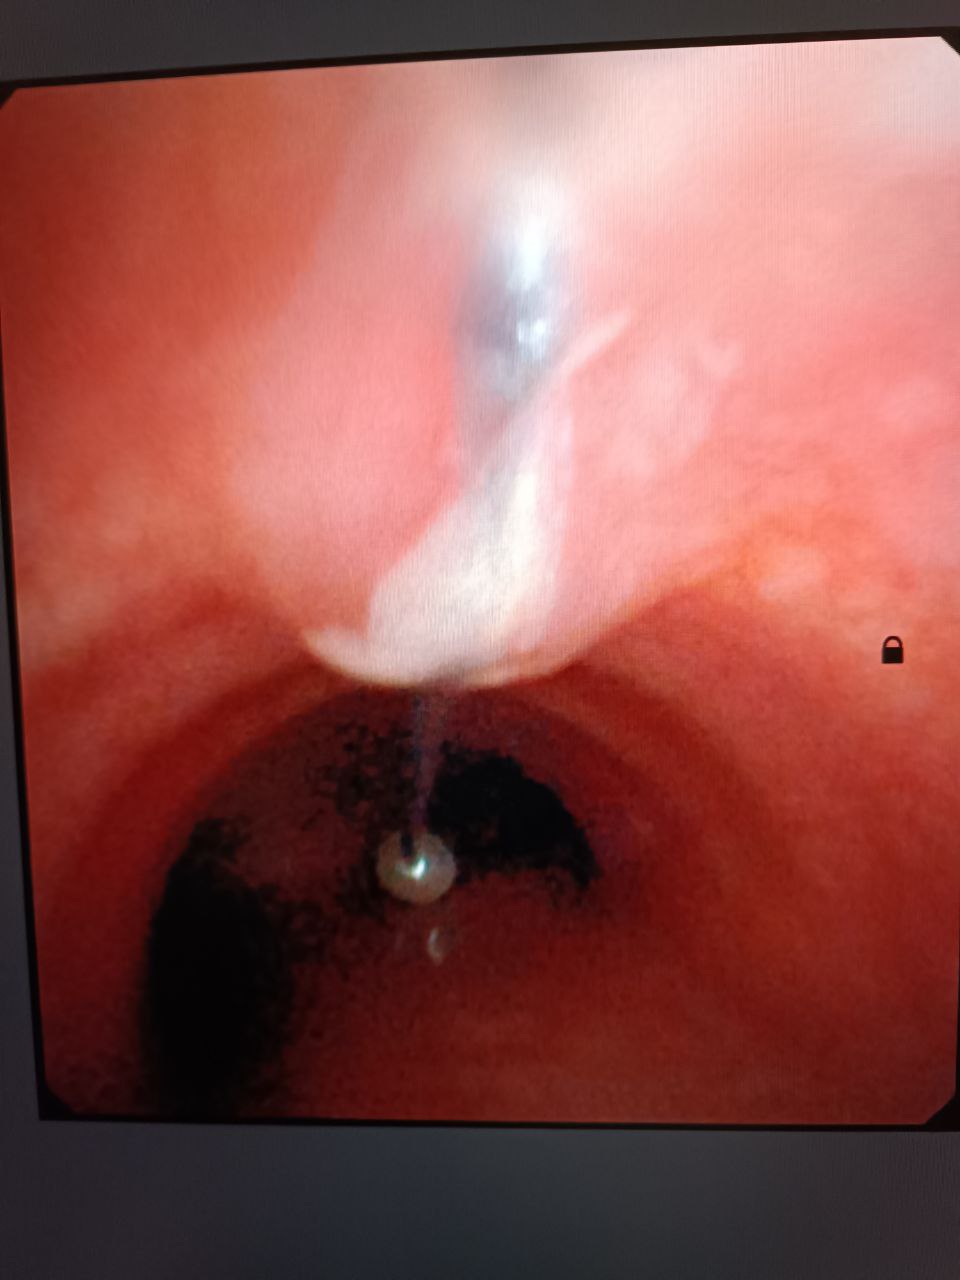

Благодаря высокой квалификации дежурного хирурга и анестезиологической бригады, эндоскопическим методом было удалено инородное тело - игла длиной 4 см.

Подростку под наркозом провели бронхоскопию и достали шпильку, которая острым концом вонзилась в слизистую и никуда не двигалась.

"Эта ювелирная работа была проведена в городской больнице благодаря современному эндоскопическому оборудованию, которое используется в городской больнице, ранее такие случаи лечились в областном центре", - говорится в сообщении.